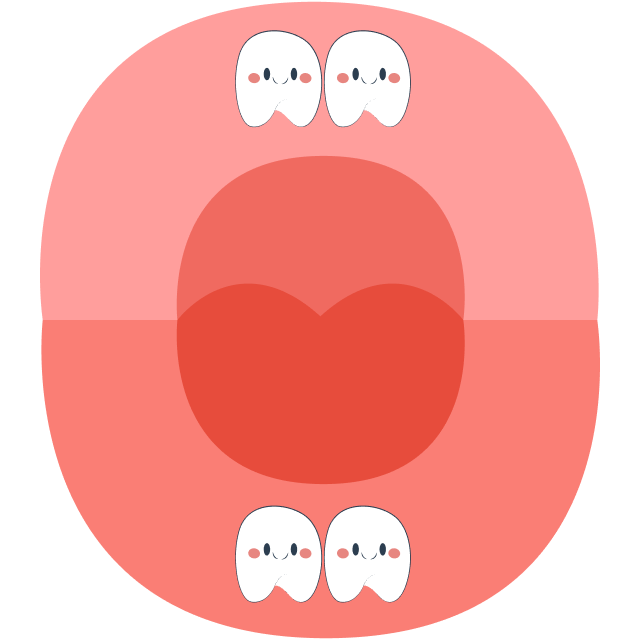

At around 6 years old, children prepare to lose their first tooth, and primary (baby) teeth will gradually be replaced by permanent teeth. The tooth replacement sequence typically begins with the eruption of the first molar (tooth number 6) and ends with the eruption of tooth number 7 around the age of 12.